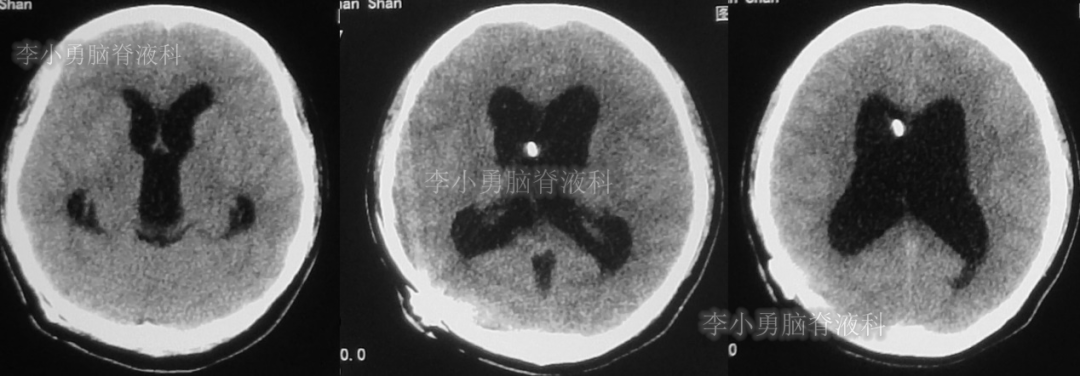

患者于2018年1月29日,突发头痛、头晕、恶心、呕吐,并高热40度。在当地医院门诊输入4天抗生素后发热缓解,但出现了双眼不能上视(眼球不能向上看)。5天后即2018年2月3日,在当地的第1家医院:浙江省海宁市某医院行头颅CT(图-1)发现脑室扩张,当地医院诊断为“梗阻性脑积水”。

图-1:2018年2月3日头颅CT